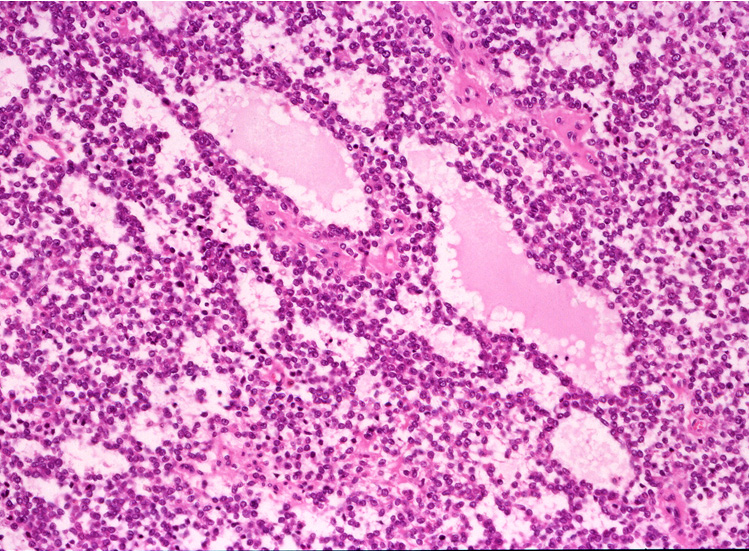

ルーペ像では(Fig.01)ヘモジデリンを貪食したマクロファージに富む線維性間質をもち、腫瘍細胞が胞巣状, 地図状に増殖している。線維性間質はdesmoplasticではなく成熟した線維組織のようである。本例ではさらに腫瘍胞巣内にタンパク液の貯留した偽嚢胞様構造が散在するほか、層状の腫瘍細胞に裏装された嚢胞様構造が出現している。(Fig.03,04)

腫瘍細胞はシート状密に増殖する、類円形小型淡明な核をもった細胞質の乏しい細胞からなる。細胞分裂像は目立たなかった。(Fig.05,06), 線維間質部分の拡大所見。腫瘍細胞が小さな集簇をつくって浸潤している。(Fig.07) Fig08では血管周囲性ロゼットが認められる。